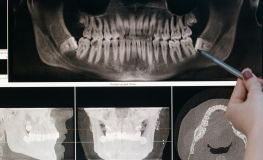

Zapraszamy do skorzystania z usług gabinetu radiodiagnostyki stomatologicznej w Onko-Dent. Oferujemy precyzyjne i bezpieczne badania przy użyciu nowoczesnego, profesjonalnego sprzętu, który gwarantuje wysoką jakość obrazowania i komfort pacjenta. Nasza pracownia to miejsce, gdzie doświadczenie łączy się z technologią – dla dokładnej diagnostyki i skutecznego leczenia.

Nasza oferta obejmuje badania RTG takie jak:

Na wszystkie zdjęcia RTG, za wyjątkiem RTG punktowego, konieczne jest skierowanie od lekarza stomatologa.